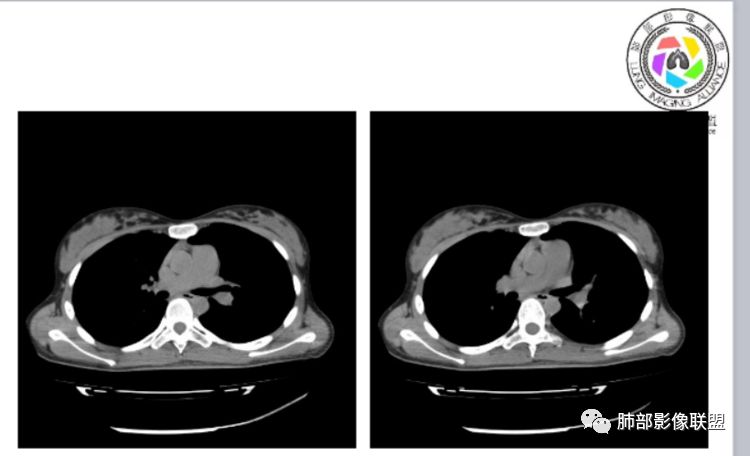

小微:右肺下叶斑片状密度增高影,抗炎治疗6天后复查,双肺下叶出现斑片状密度增高影,排除炎性病变,D2聚体特别高,考虑肺栓塞,肺梗死,建议增强扫描。王开金江津中心医院呼吸科:@岳微-辽宁PLA234医院放射科?支持,患者年轻女性,胸痛主诉,使用雌激素,高危人群,心率快,d二聚体升高,右下叶斑片加肺动脉明显增宽,抗感染无效,要考虑PTE,建议肺动脉ctpa。傅昌瑜:19岁,女性,右侧胸痛2天,发热以中度热为主,D—二聚体升高,肺动脉主干增宽,病灶位于胸膜下,抗感染后增多,近来有服用炔雌醇环丙孕酮片2周期史,诊断:肺栓塞,下一步完善肺CTPA检查。阿仙奴:青年女性,急性起病,胸痛入院,月经不调史,目前服用孕酮片。流感抗体阳性,d二聚体升高,无低氧血症。右肺下叶基底段胸膜下磨玻璃样改变,肺动脉增宽,治疗过程出现发热,复查左下叶胸膜下新发病灶。考虑:肺栓塞(服用孕酮相关)?奔跑的37°Doctor(陆喜红 ) :年轻女性,胸痛 急性病程,有服用雌激素避孕药史(是否有血液循环的改变,高凝状态),实验室D二聚体很高(也是提示血液高凝状态) ,第一次CT,右下肺胸膜下斑片状密度增高模糊影,肺动脉形态密度未见明显异常,抗炎后复查,肺动脉干及其分支,感觉增粗了一点,局部形态有点饱满,双下肺胸膜下片状影增多,锁定肺动脉栓塞应该不会错,建议CTA检查飞鹰行动:青年人,女性,右肺下叶斑片状密度增高影,抗炎治疗6天后复查无好转,,双肺下叶出现斑片磨玻璃影,主肺动脉增粗,结合患者服用的药物和D2聚体特别高,考虑肺栓塞,建议CTA。李:口服避孕药,有危险因素,肺动脉较主动脉增宽,D二聚体增高,胸膜下片状影,考虑肺栓塞;@晨义工张帅,医附属潞河医院呼吸?是否痰中带血很关键,不知有没有张帅:患者入院后第七天出现痰中带血风之子:病程中有发热,D—二聚体升高,肺动脉主干增宽,病灶分布于胸膜下,抗感染后增多,结合服药史诊断:肺栓塞,建议CTPA检查。不支持的地方是没有低氧血症,不明白为什么第二次复查ct双侧乳腺不对称,按理乳腺炎多见于哺乳期张帅:大家方向都在考虑肺栓塞:我提问两个问题:1 周围毛玻璃怎么回事?2左下肺小叶间隔增宽怎么回事?笨丫头:周围的磨玻璃应该考虑是肺梗死后出血渗出,同时合并机化性炎症小叶间隔增宽,我考虑应该是梗死后炎性渗出wonderful:我不支持肺栓塞 不能解释发热原因

张帅:好多老师都在说肺动脉增宽。肺动脉增宽标准是多少?程磊:29。或者比同层主动脉比值大于等于1

水晶石头:患者青少年女性,右侧胸痛2天就诊。有咳嗽,无痰。初次胸部CT:右下肺片状模糊影。入院后经头孢美唑、莫西沙星抗感染治疗6天后复查胸部CT:右下肺病灶加重,且左下肺出现类似病灶。结合其气管镜气道无异常,病程中有发热,D—二聚体升高,近来因月经不调有服用炔雌醇环丙孕酮片史。诊断考虑良性非感染性。肺栓塞可能性大,鉴别血管炎及子宫内膜肺异位可能。流心明智:女性,19岁,右侧胸痛2天,中度热为主,D—二聚体升高,影像:肺动脉主干小于29mm,病灶位于右下肺胸膜下,斑片影,胸膜侧宽基底,抗感染后增多,左下肺亦出現类似病灶,似有反晕、融冰征。近来有服用炔雌醇环丙孕酮片2周病史,考虑诊断:肺栓塞。具体性质及发病机制有待进一步检查。尘缘:@吴永丽 灌云县医院 呼吸?应该是的,左下肺的磨玻璃影像后面也支持有出血改变所以可能就是一个子宫内膜异位出血合并感染

CTPA(CT断层肺血管造影)是对疑似PE患者肺血管系统成像的首选方法,可直观判断肺栓塞的程度和形态,以及累及部位及范围,可以从直接或间接征象进行诊断,但是对亚段及远段肺动脉血栓敏感性较差,联合肺动脉造影可以使PE诊断敏感性增强。

CTPA直接征象:

1、肺动脉中央部分充盈缺损

2、偏心性或附壁充盈缺损

3、骑跨型血栓

4、完全型充盈缺损,动脉截断,远端动脉分支内无造影剂

CT平扫及间接征象:

1、一个或多个胸膜下斑片高密度影(梗死、出血、肺不张、肺水肿、炎性渗出),典型为胸膜下楔形影 ,尖端指向肺门

2、肺动脉高压(中心肺动脉扩张),有时可见肺动脉区高密度影。

3.影像:病变胸膜下多发斑片影,提示与血管有关,早期病变为渗出,应该是早期的炎性渗出,病灶抗感染治疗后实变区增多、变大,临床症状又出现咯血,CT上应该合并了肺泡出血、梗死、肺不张及肺水肿;